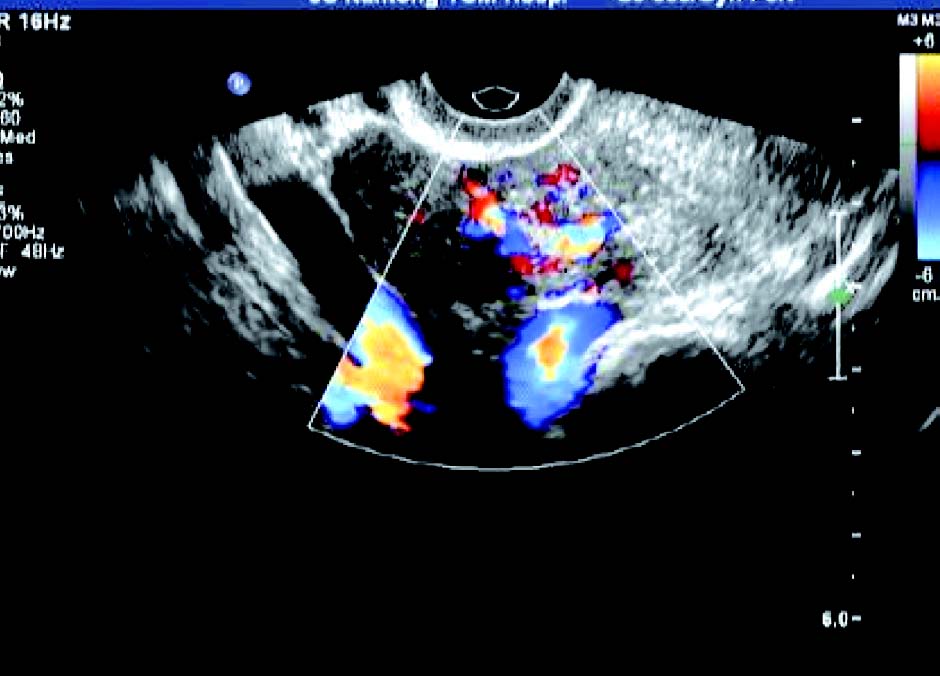

患者,女,42岁,常规体检。超声检查声像图显示:子宫前位,三径正常,边界清,子宫内膜欠清。肌内可见多个低回声包块,较大者约1.7cm×1.4cm(前壁)、1.8cm×1.4cm(前壁)、1.9cm×1.4cm(后壁),边界清,有假包膜,内部回声均匀,子宫边界规整。CDFI探查:较大团块周围见半环状彩色血流信号。包块内未见彩色血流信号。宫腔内可见节育器影像,距宫底约1.5cm。

超声提示:子宫肌瘤(肌间);宫内节育器,位置正常。